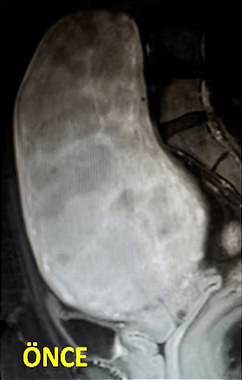

41 yaşında, kabızlık, gaz ve sık idrara çıkma şikayetleri var. Emar’da karını dolduran dev miyom (*) mevcut. Miyomektomi önerilmiş, ancak operasyonda rahimin alınabileceği söylenmiş. Embolizasyondan sonra dev miyomun ve bir başka küçük miyomun öldüğü ve küçüldüğü izleniyor. 7 ay sonra hasta şikayeti kalmamıştır.